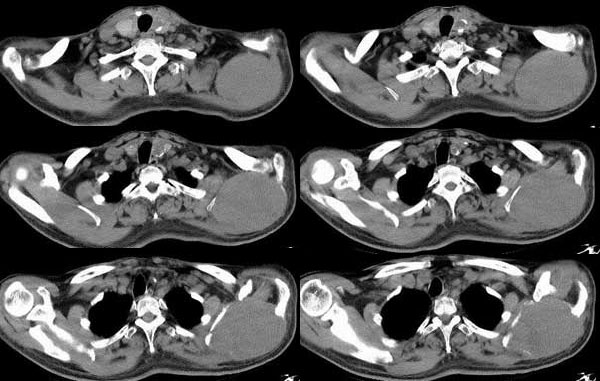

CL0070:[原创]胸腰椎转移瘤

m,53y。

椎体骨质破坏,考虑转移瘤。

胸腰椎转移瘤

肺癌骨转移者半年生存率<50%。